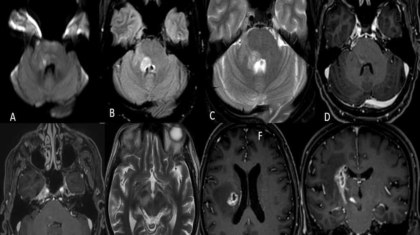

50 year old man presented with history of pyrexia of unknown origin, dull headache ,right ear pain, left side weakness and difficulty in swallowing. On neurological examination: Right side diplopia on looking at far objects